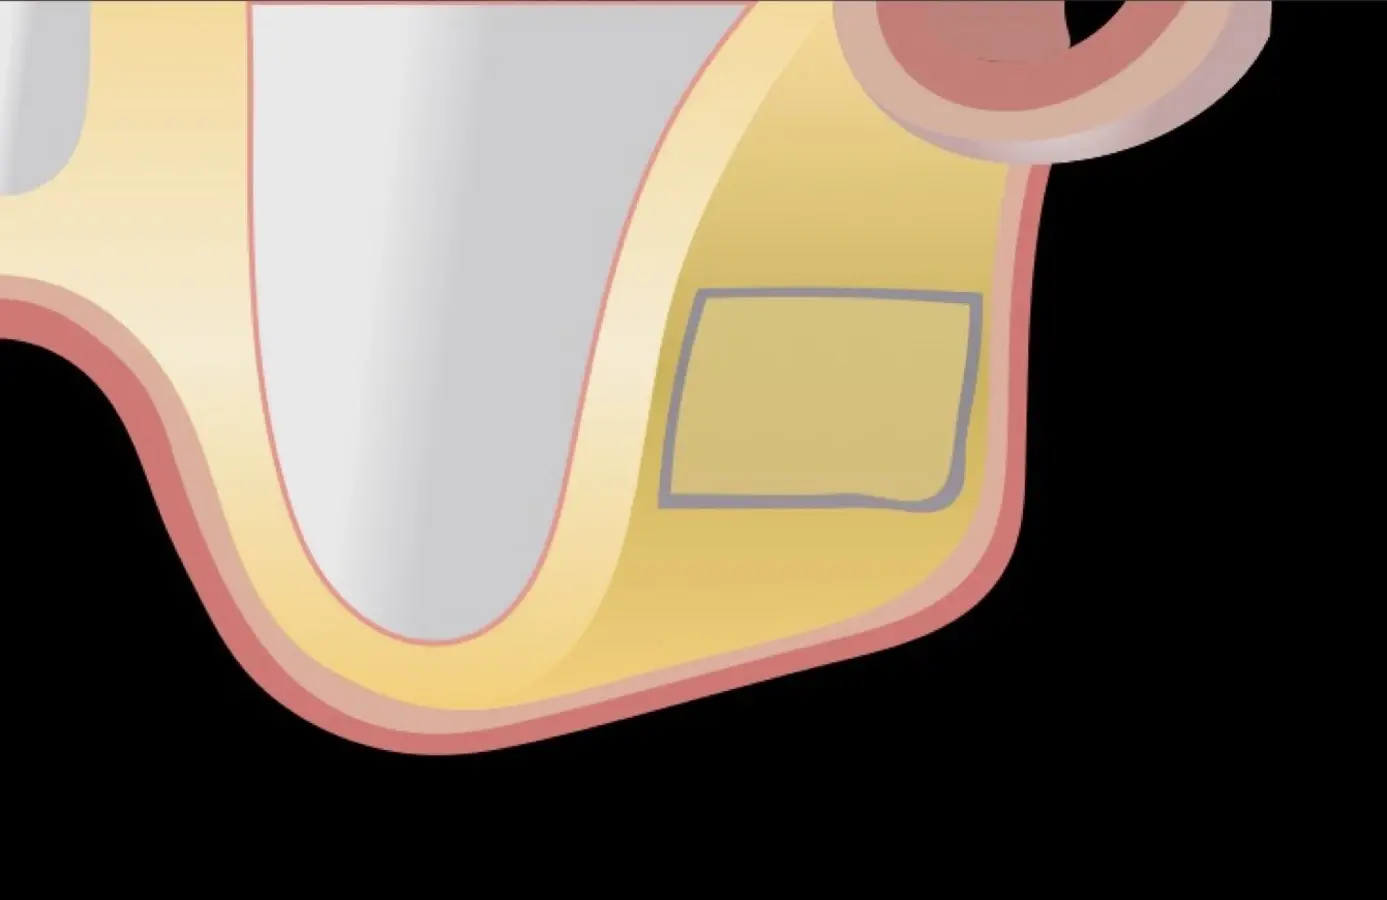

Se inicia la elevación de la membrana de Schneider con el inserto redondeado no cortante en forma de disco, empleando movimientos suaves. El levantamiento puede complementarse con elevadores convencionales, siguiendo la dirección mesiodistal. La fase de desprendimiento inicia con el piso y sigue hacia la pared mesial para terminar, y de ser necesario, hacia la pared posterior. Existen diversos insertos con angulaciones y longitudes para mayor accesibilidad16 (Figura 1).

El tipo de inserto a ser utilizado dependerá del espesor de la pared ósea. Si la pared es menor a 0.5 mm, es mejor utilizar insertos de desgaste para prevenir la ruptura de la membrana de Schneider; si el espesor es mayor a 0.5 mm, se puede utilizar insertos de corte de espesor medio (Figura 3).